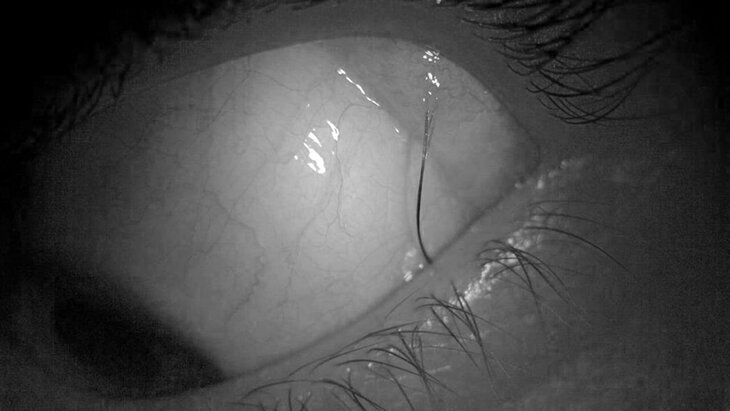

Специалисты Детского клинического центра имени Рошаля оказали помощь 14-летней пациентке, у которой в слизистой оболочке левого глаза вырос волос. Об этом сообщили в пресс-службе Минздрава Подмосковья.

По информации ведомства, аномальное образование длиной примерно в 1 сантиметр, похожее на ресницу, не представляло угрозы для здоровья девочки, однако оно постоянно вылезало из-под века, вызывая серьезный дискомфорт в повседневной жизни.

В ходе операции хирурги успешно удалили волос под общей анестезией, а затем отправили его на гистологическое исследование. После вмешательства подростка выписали домой на амбулаторное лечение. Сейчас девочка чувствует себя хорошо.